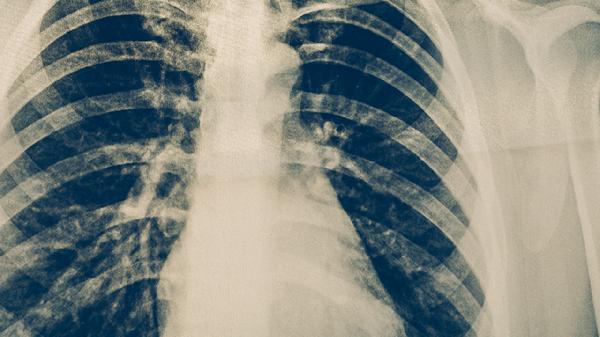

肺結核康復期患者需保持規(guī)律三餐,烹飪方式以蒸煮燉為主。每周進行3-5次有氧運動如快走、太極拳等,運動強度以微微出汗為宜。定期復查胸部影像學,出現持續(xù)兩周以上的午后低熱、夜間盜汗等癥狀應及時就診。居家環(huán)境保持通風干燥,每日開窗換氣2-3次,每次不少于30分鐘。